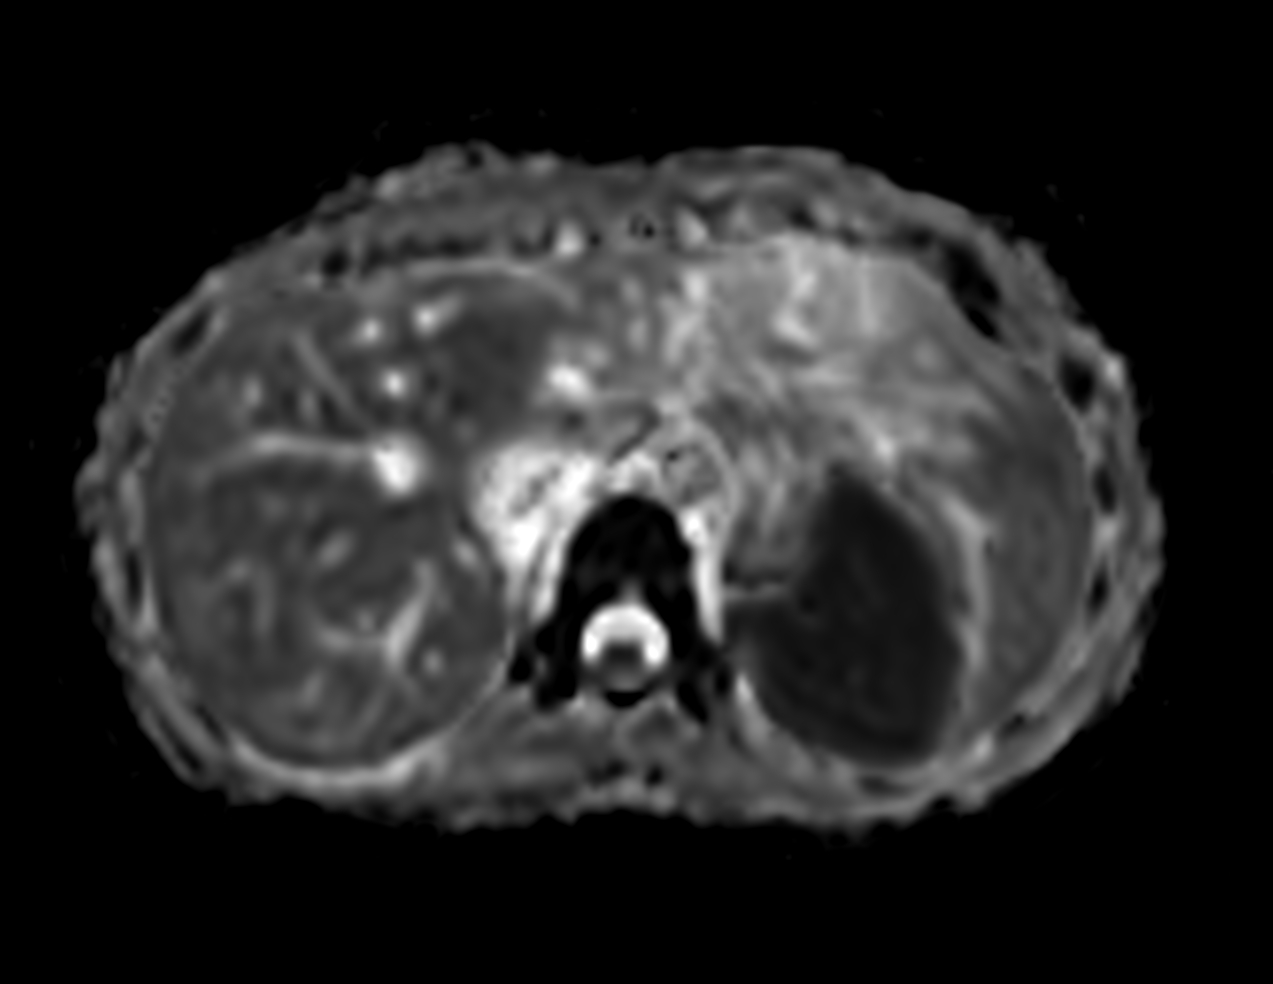

Axial DWI (b600)